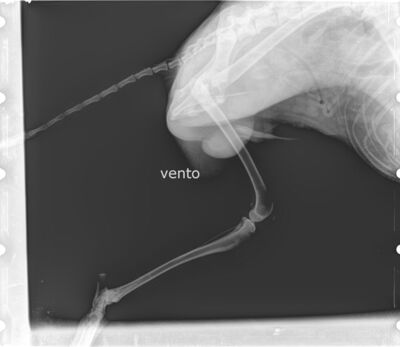

Vento wurde heute kastriert. Da uns aufgefallen war, dass er hinten links hinkt und schont, wurde während der Narkose geröntgt. Diagnose: Er hat eine alte Verletzung am Oberschenkelkopf, die degeneriert ist und zu Lahmheit, Gelenkschmerzen und Verlust von Muskelmasse führt. Exzisionsarthroplastik wird empfohlen.